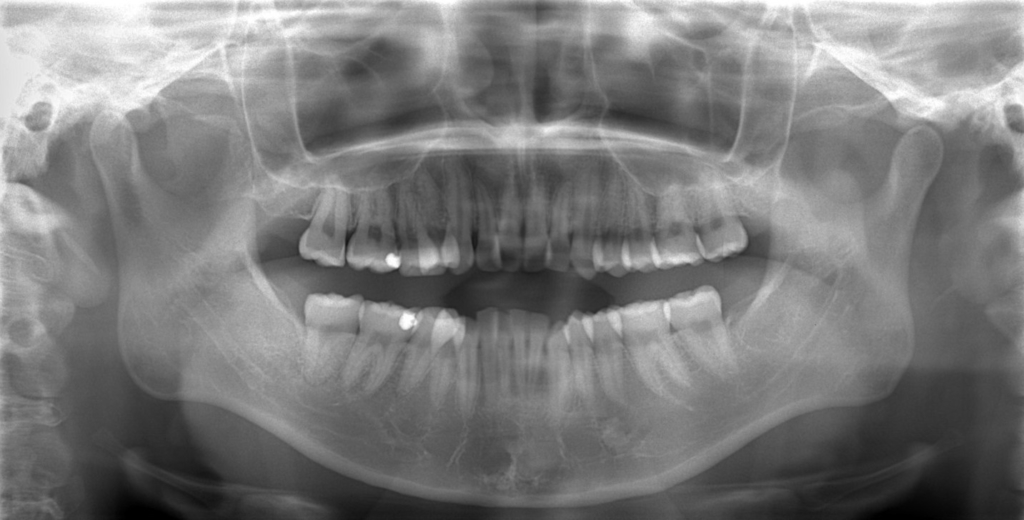

レントゲン写真で確認すると、

この患者さんの場合、

#1.顎と歯の不調和による叢生

#2.上顎前突(出っ歯)

上下の左右の奥歯を1本ずつ計4本抜歯(4番目の奥歯を抜きました)

(上下とも智歯はありません)